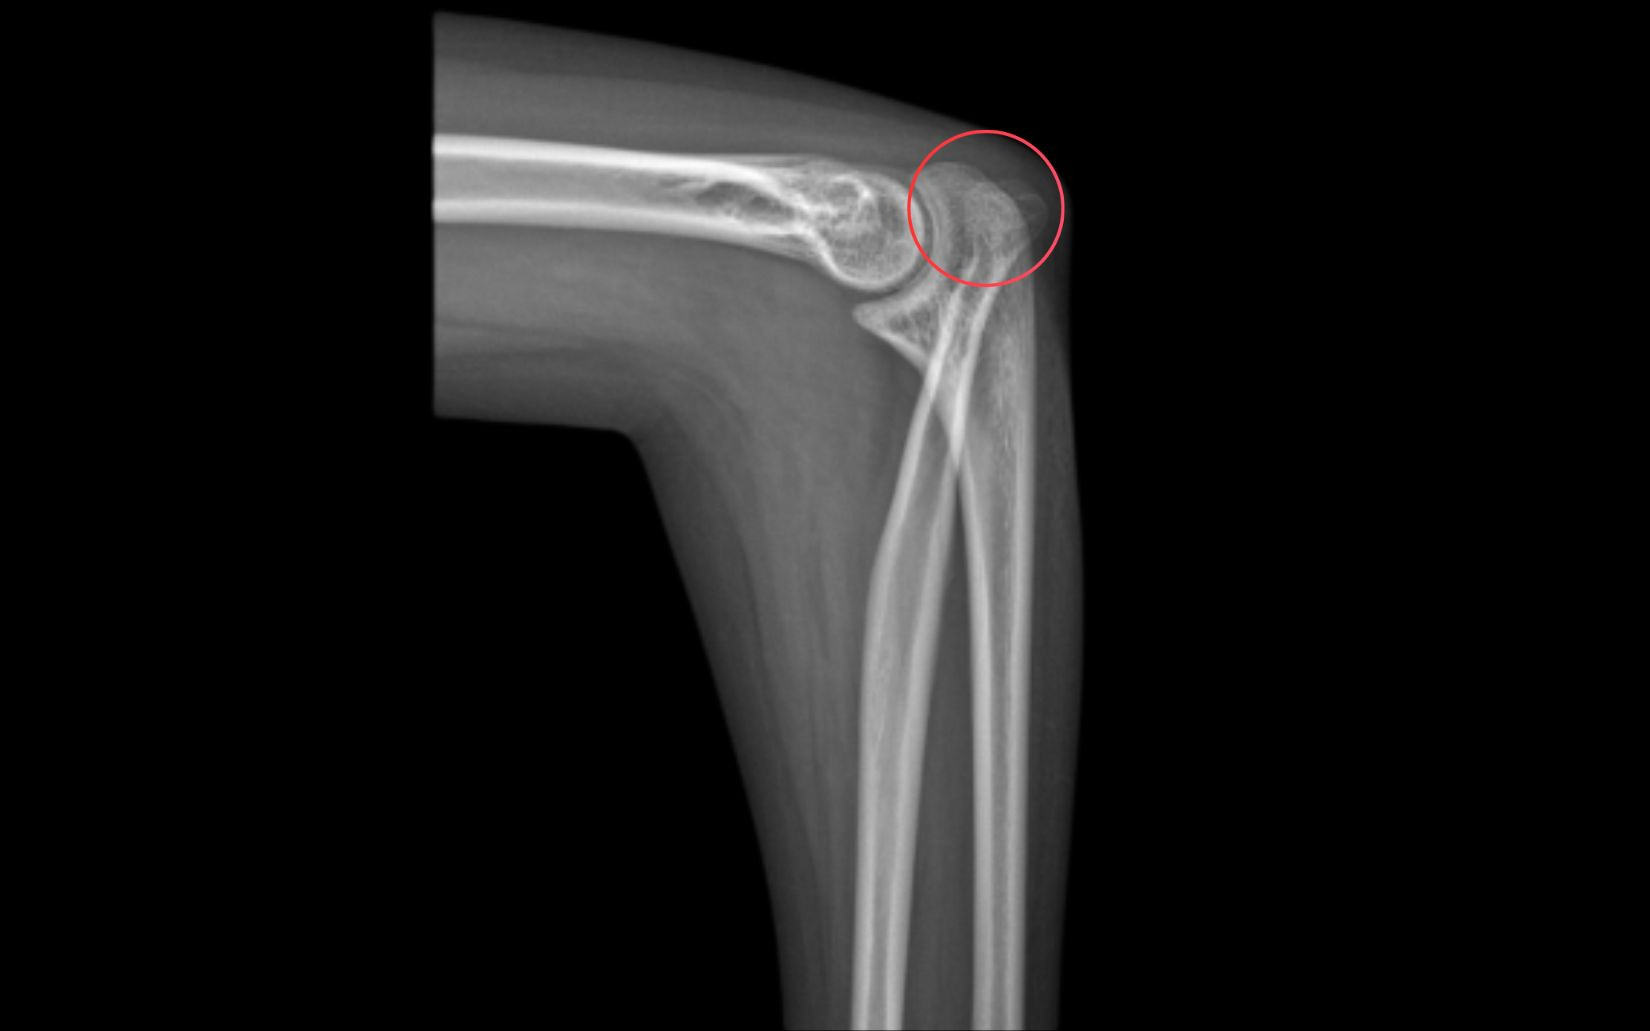

Sau khi thăm khám cùng TS.BS Lê Quang Huy (Trưởng khoa Chấn thương chỉnh hình, thần kinh sọ não) BVĐK Hồng Ngọc - Phúc Trường Minh, Hoa được chẩn đoán gặp tình trạng biến dạng trục khuỷu tay bẩm sinh, hạn chế khả năng sấp, ngửa và xoay cẳng tay. Nếu không can thiệp tình trạng này sẽ ảnh hưởng đến chất lượng cuộc sống và thẩm mỹ.

Cũng theo bác sĩ, tình trạng của Hoa cần phẫu thuật chỉnh trục khuỷu tay nhằm đưa trục vận động về gần bình thường, đồng thời cải thiện biên độ xoay và sức cơ, điều mà Hoa đã mong mỏi từ rất lâu nhưng chưa từng nghĩ sẽ có cơ hội thực hiện.